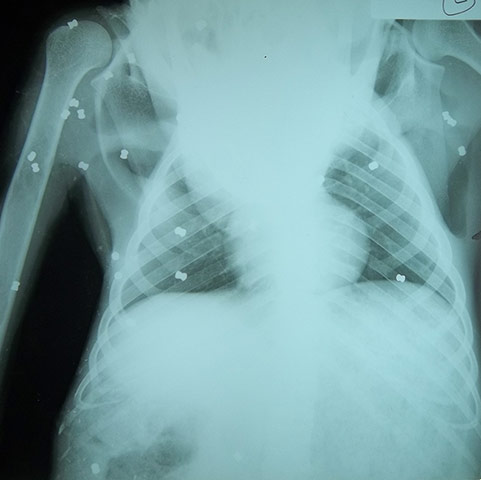

An x-ray image showing bullets in Aan's head. The Bornean orangutan is an endangered species, with oil-palm plantations posing a serious threat to its continued existence. Orangutans come into conflict with humans through encroachment on plantations and village crops and are often viewed as pests by local farmers Photograph: Orangutan Foundation UK

X-rays showed 104 pellets scattered all over her body, including vital organs, her eyes and ears Photograph: Orangutan Foundation UK